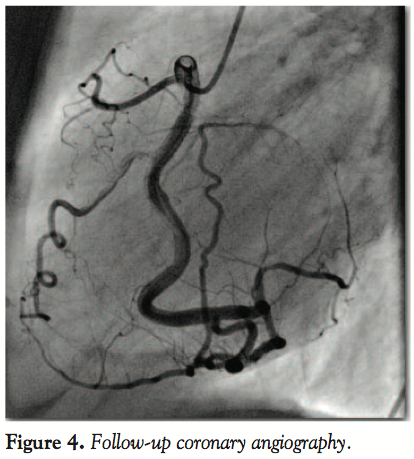

Case Report. The patient was a 54 year-old female admitted to our hospital with typical 3-hour resting angina and vegetative symptoms with excessive sweating. She had a history of hypertension, hyperthyroidism, hysterectomy, and nicotinism. At the time, she had been treated with beta-blocker, ACE inhibitor and HRT (estradiolum plus norethisteroni acetas). The patient had reported no exercise angina when hospitalized due to severe hypertension a few years before. Electrocardiographic (ECG) examination showed sinus rhythm with ST-segment elevation in inferior wall leads with reciprocal ST-segment depression in leads I, aVL, and V1-V4. Vascular access was obtained by right femoral artery. Coronary angiography revealed proximal occlusion of dominant right coronary artery (RCA) with thrombus just 2 mm below the take-off of the conus arteriosus branch — the only patent collateral to the left coronary system (Figure 1).